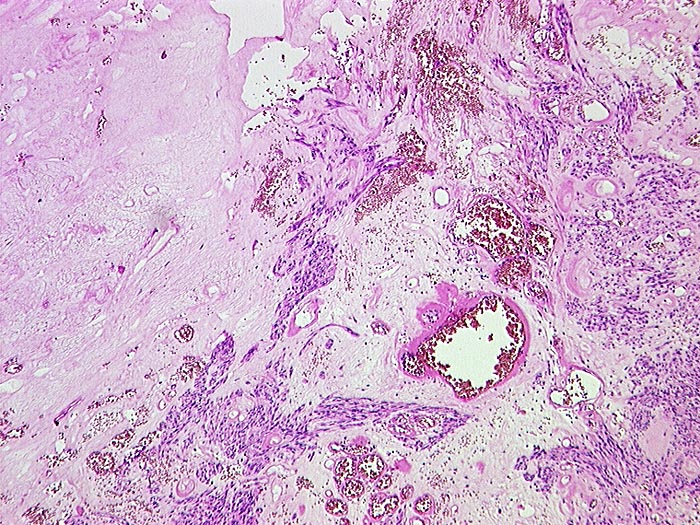

Gastrointestinaler Stromatumor (GIST)

Spindelzelliger Tumor. Grössere degenerative praktisch zellfreie Sklerosezonen mit grösseren Gefässen und Zystenbildung.

Tumordurchmesser 4.5cm. Aktin und CD 117 positiv. Morphologische Ähnlichkeiten mit einem Leiomyom mit degenerativen Veränderungen (Sklerosierung, Zystenbildung). Kaum Mitosen. Keine Nekrosen.